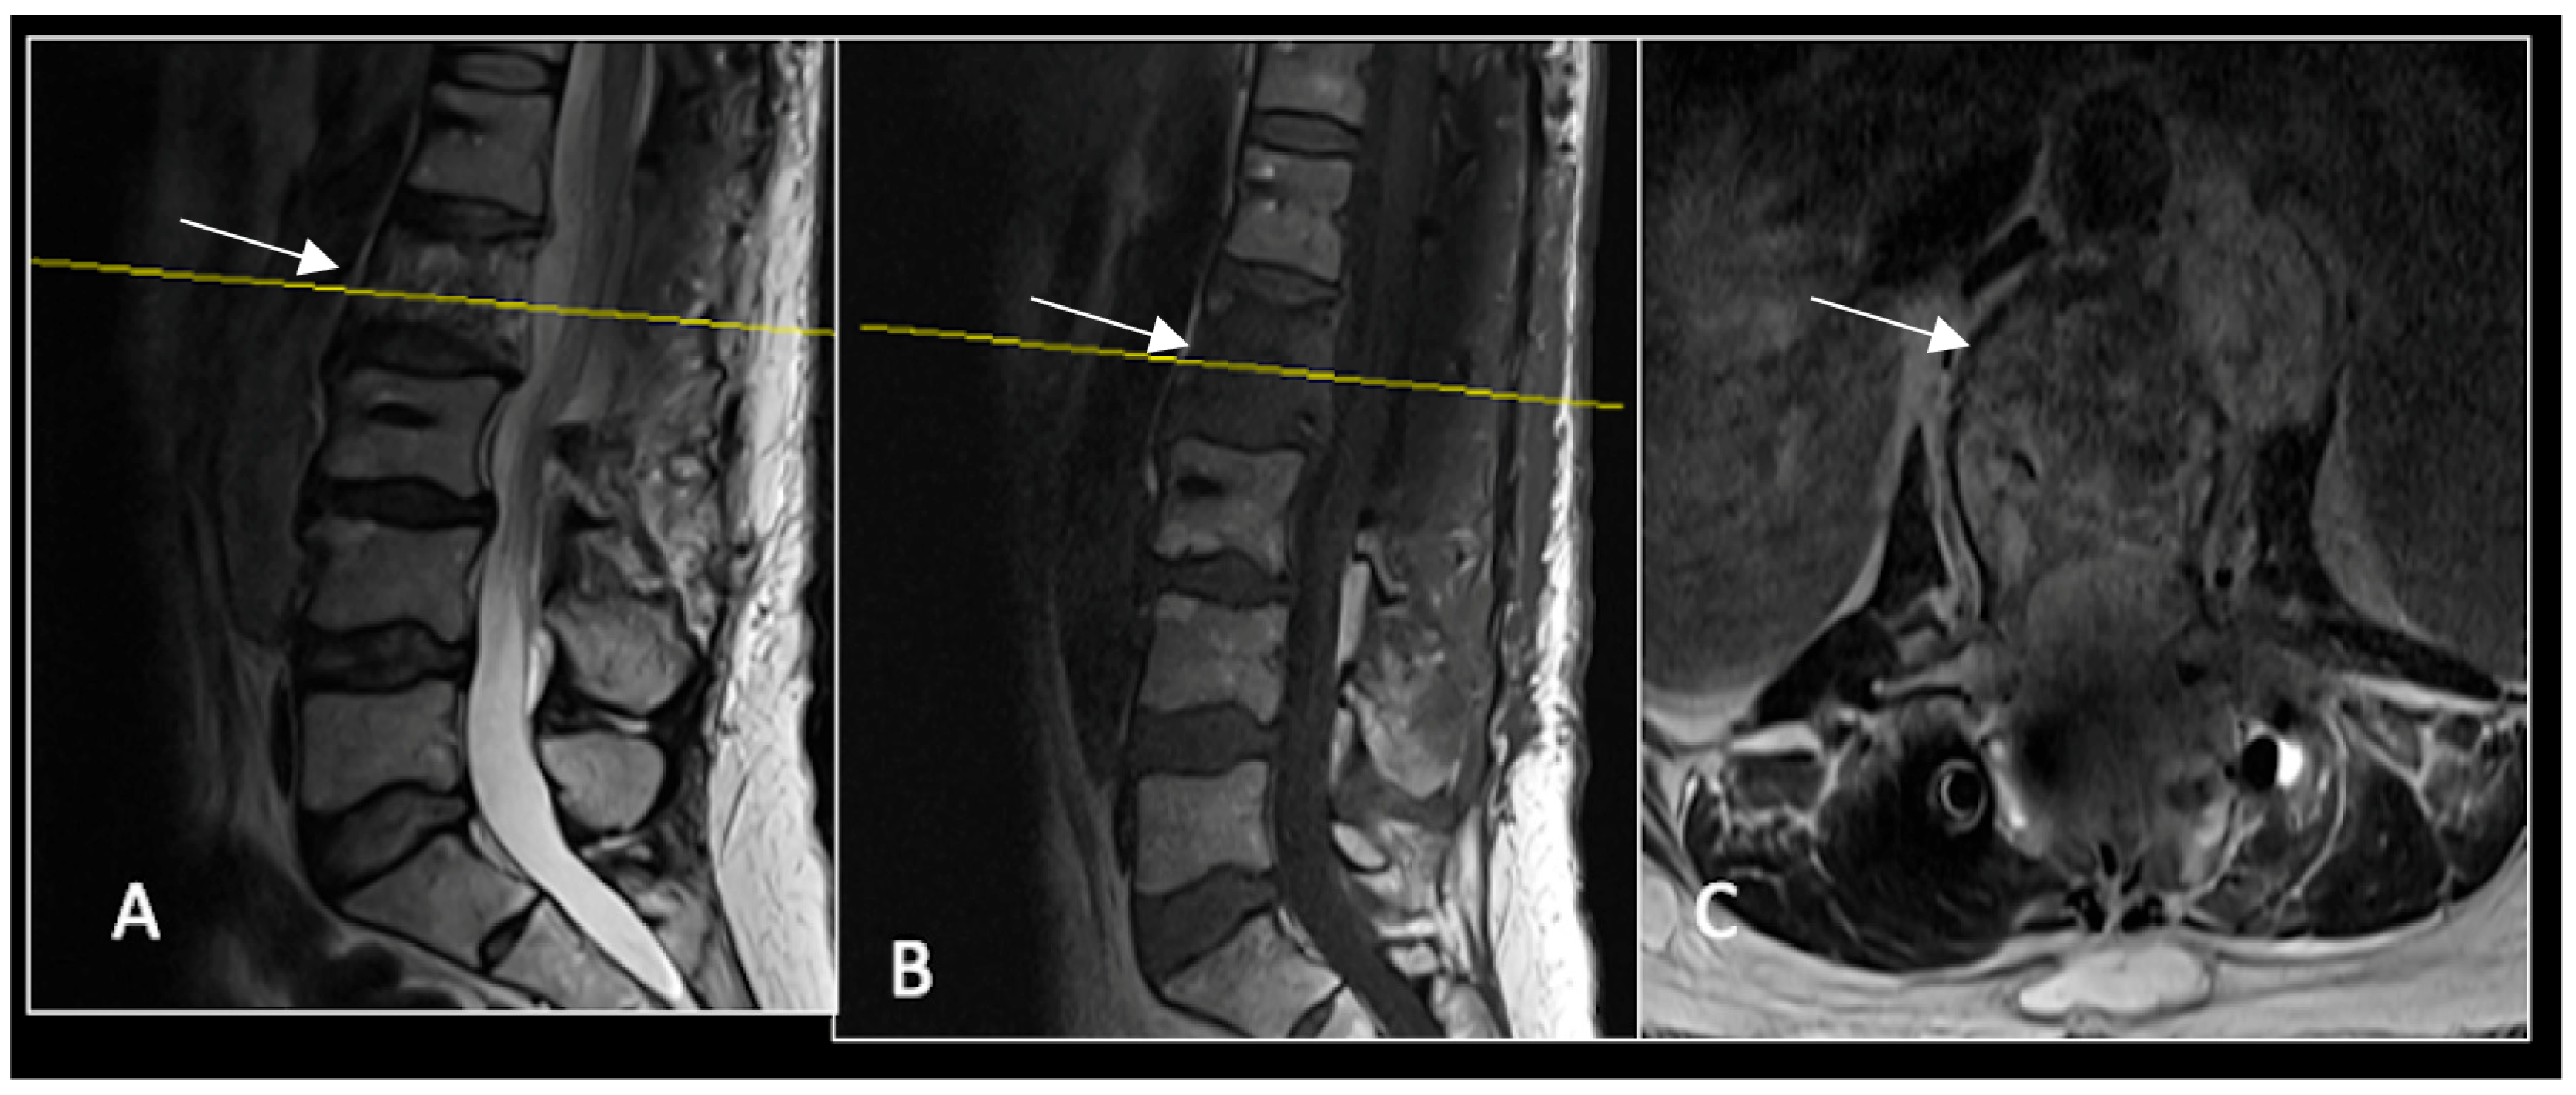

Figure 13.

A 6-month postoperative surveillance MRI shows no obvious evidence of residual tumour (arrow) disease progression, but there is significant artefact. The yellow line on the sagittal images denotes the level of the axial image. (A) T2W sagittal; (B) T1W sagittal; (C) T2W axial.